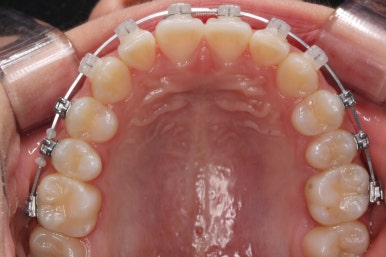

치료 종료 후의 모습입니다.

치아들이 가지런하게 되었고, 나오지 못하던 치아도 잘 나와서 가지런해졌습니다.

해당 부위 앞뒤로 쓰러져 있던 치아들도 축이 바로 잡혔고, 자연스레 위-아래 치아의 중앙선도 맞아졌습니다.

부산치아교정잘하는곳 키다리아저씨치과에서 이번 청소년 환자분께 치료하느라 소요된 기간은 총 16개월이였습니다.